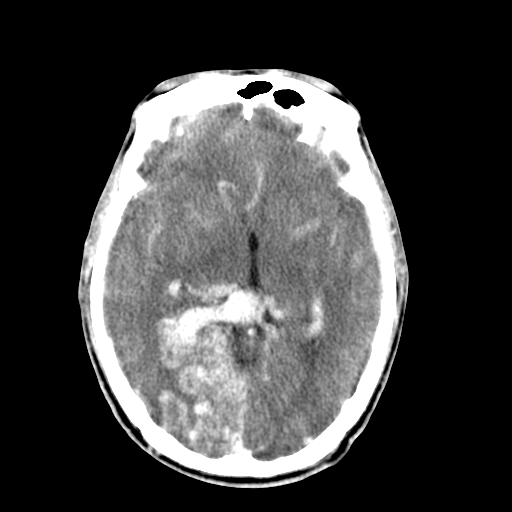

标题: CT17002:M48Y,血管畸形,血管瘤,请鉴赏! [打印本页]

标题: CT17002:M48Y,血管畸形,血管瘤,请鉴赏!

男48y,头痛多年,加重一天!

典型的血管畸形---avm  -----右侧枕顶叶及侧脑室三角区等高混杂密度影夹杂少许低密影显示,无明显水肿,增强可见明显的供血动脉与引流静脉显示